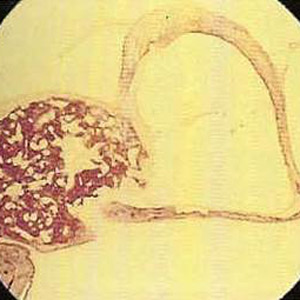

Histologie Steigbügel mit Otosklerose